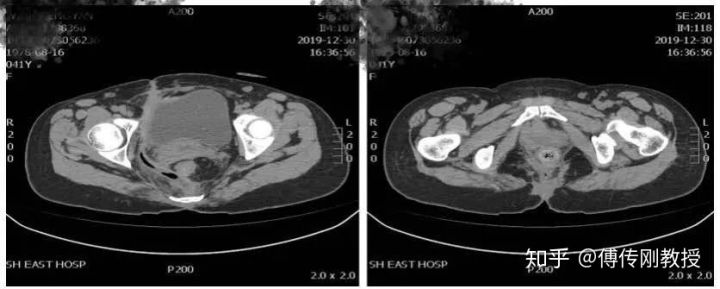

入院腹部CT

2020.01.14医生给我腰麻下行骶尾部窦道切开、脓肿引流术。手术记录显示术中探查齿状线上3cm可触及直肠后壁瘘口约0.5cm,内有少量陈旧性干结大便。囊腔位于直肠右后间隙,约12*10*5cm,内有脓液和少量坏死组织。